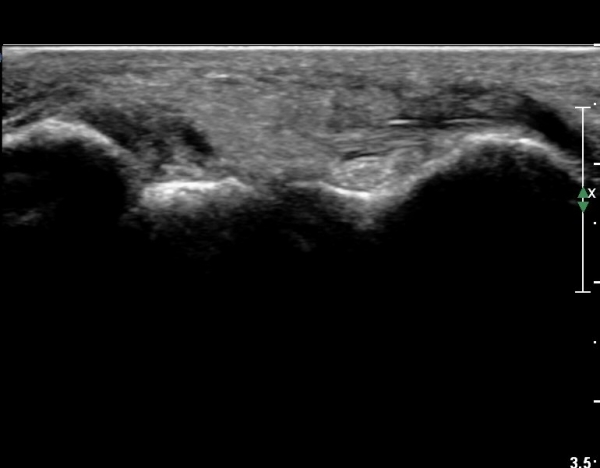

Àü°ÅºñÀÎ´ë ºÎÇϰ˻翡¼­ ÀδëÆÄ¿­ ºÎÀ§°¡ ¹ú¾îÁö°í °Å°ñÀÌ ¾ÕÀ¸·Î ´Ü°ÜÁö´Â ¼Ò°ßÀ» º¸ÀÓ(»çÁø 3, 4, ÷ºÎ µ¿¿µ»ó).